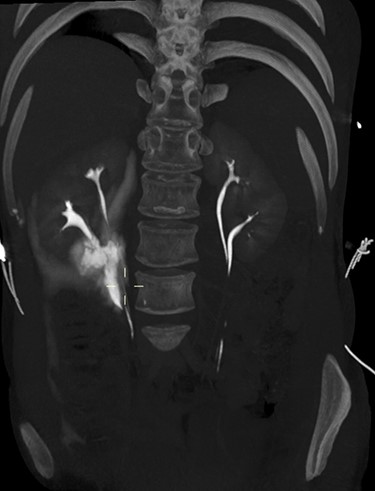

On arrival at 02:00, her temperature was 40.3°C with stable vital signs. After assessment by a multidisciplinary trauma team (orthopaedics, general surgery and urology), she had a CT Urogram that showed duplex kidneys and extravasation of contrast within the right peritoneum in keeping with urine leak (Figs 1 and 2). The lower moiety ureter was discontinuous with a mildly thickened and hyper-enhancing wall. The area of discontinuity was related to the highest density fluid on urographic phase, in keeping with this being the source of urine leak. The right upper moiety ureter appeared to be intact. There was no concomitant parenchymal injury.

CT Urogram demonstrating extravasation of contrast. The blue arrows show the severed ends of the right inferior collecting system. The red arrow shows the contrast extravasation.

3D maximum intensity projection image of bilateral duplex kidneys and the contrast extravasation from the inferior moiety.